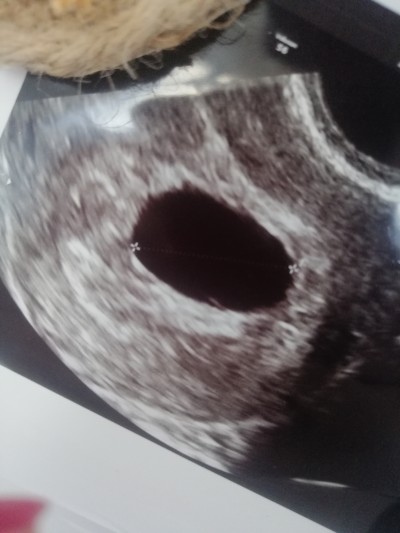

Merhaba hanımlar bu görüntüde yolk kesesi var mı? Doktor iki gün önce bebek görünmediği için boş gebelik var kürtaj demişti 6+6 yım şuan. 2 3 hafta daha bekleyip öyle gidicem tekrar. Yolk kesesi olunca bebek görünür diyorlar benim yolk kesem var mı. Kesemin boyutu 17.04 mm

Gebelik haftası 6+6

Yolk kesesi gözükmüyor canim

Canım 15 mm sonrasında yolk saç oluşmuş olmalı. Boş gbi görünüyor inşallah degildir

Canım üzmek istemem ama bu haftada ben bebeği gördüm belki geç döllenme olmuştur inşallah görürsün

Canım gözükmüyor ama